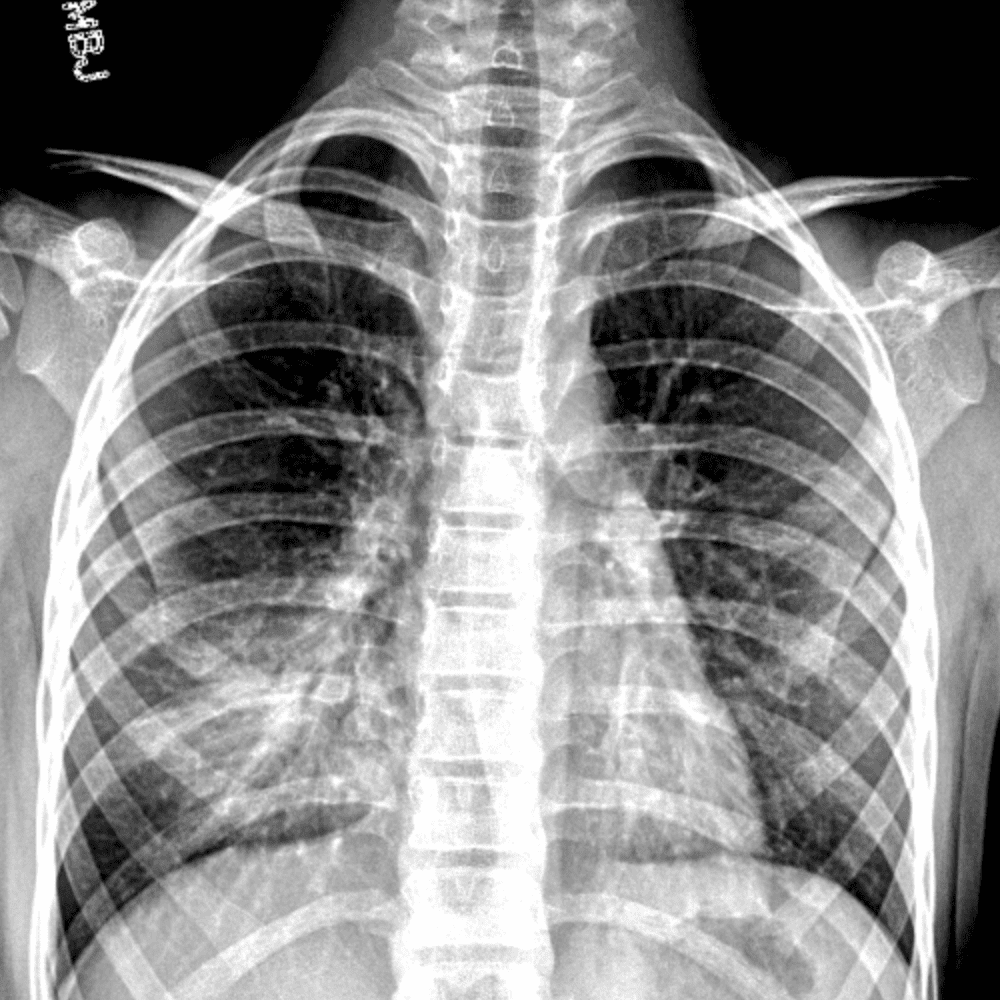

Peds Chest

Practice

Simulates call by including subtle or difficult cases and some normals.

50 cases